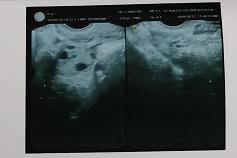

经过长时间的思想斗争后,小翠最终决定来到玛莉亚进行人流手术。手术之前小翠照例进行B超检查,可B超提示没有发现胚胎,只显示宫腔内有呈粗点状组织,这个结果让医生和小翠都有些出乎意料,于是B超医生立即与赵淑萍医生进行会诊,怀疑小翠是葡萄胎的可能,决定先进行手术处理。